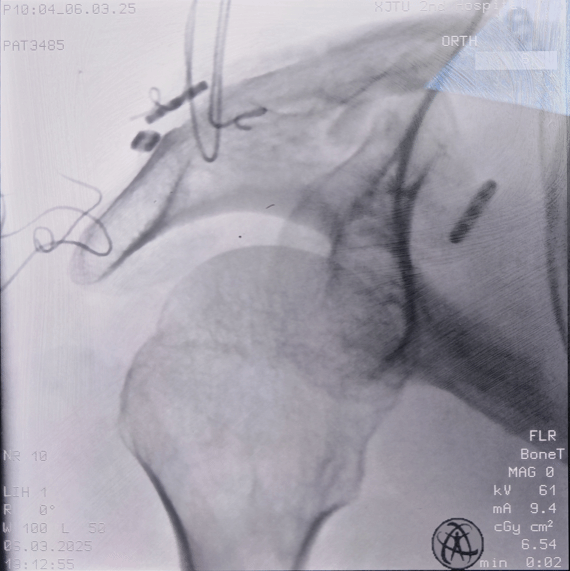

术中透视

锁骨远端骨折合并肩锁关节脱位的治疗难点在于既要稳定骨折端,又要精准复位肩锁关节。长期以来,钩钢板一直是该类损伤的首选手术方案,但其局限性较为突出。首先,钩钢板植入过程中易损伤肩峰周围软组织;其次,术后异物感明显,肩关节活动受限,影响功能恢复;最后,患者需接受二次手术取出钢板,不仅增加手术风险,也加重心理负担。针对这些问题,该患者手术采用创新悬吊缝合桥技术,是在肩锁关节脱位手术中喙锁悬吊系统的基础上创新改良而成。术中分别于喙突基底部、锁骨近端、锁骨远端及肩峰放置带袢钛板,并使用缝线交错连接各钛板,构成对骨折端起弹性固定作用的缝合桥。该技术以喙突为基底,通过上方多个固定点下压复位骨折端及肩锁关节,形成稳定的固定结构。